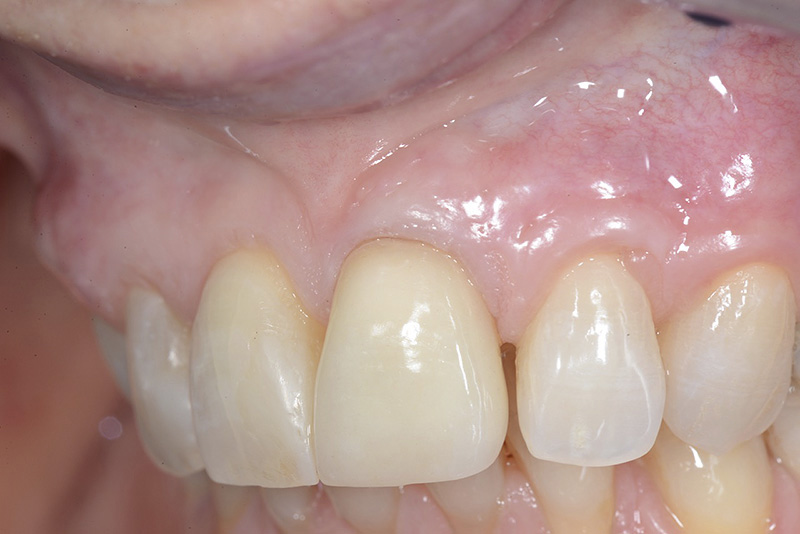

Vengono utilizzati 2 tipi di provvisori: il primo, cementato ai denti vicini, viene utilizzato dal momento dell’estrazione del dente fino ad impianto osteointegrato (circa 6 mesi); il secondo, avvitato direttamente all’impianto, ha una funzione di prova estetica ma soprattutto di guida per la maturazione dei tessuti gengivali peri-implantari portandoli verso la maturazione completa prima di posizionare la corona finale in disilicato di litio.